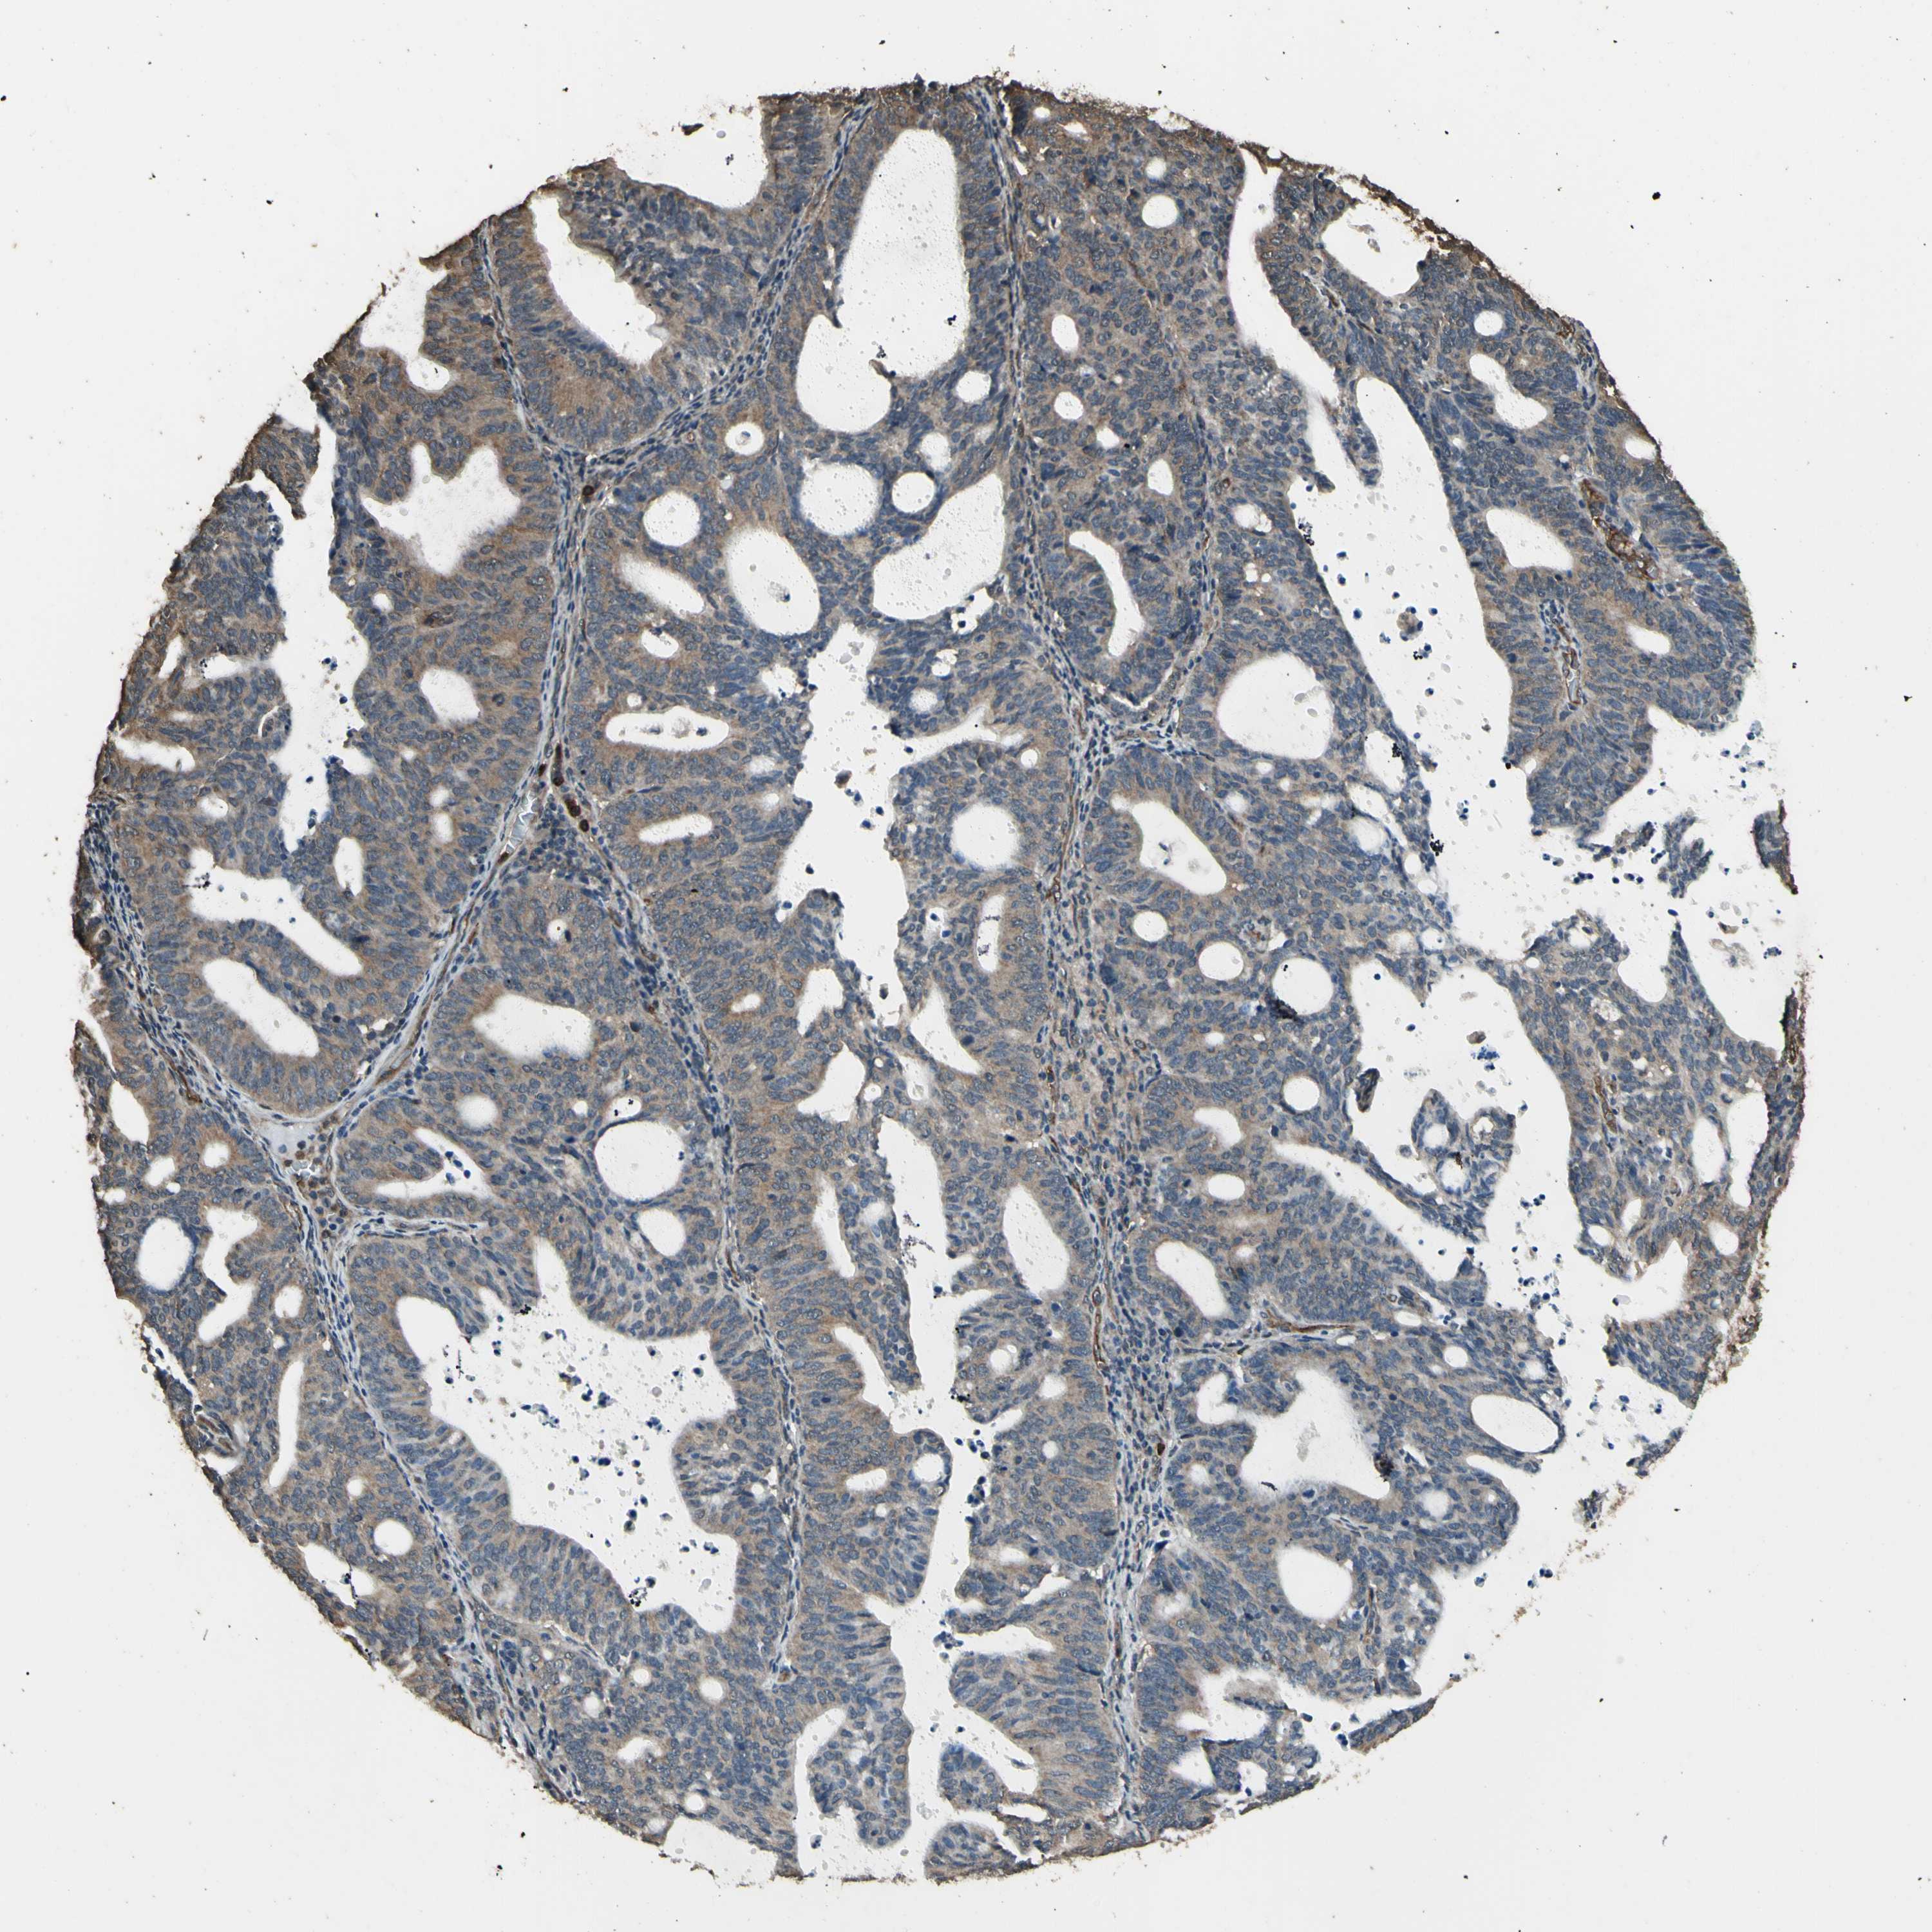

ENDOMETRIAL CANCER - Protein expressioni

A mouse-over function shows sample information and annotation data. Click on an image to view it in a full screen mode. Samples can be filtered based on level of antibody staining by selecting one or several of the following categories: high, medium, low and not detected. The assay and annotation is described here.

Note that samples used for immunohistochemistry by the Human Protein Atlas do not correspond to samples in the TCGA dataset.

Antibody stainingi

Antibody staining in the annotated cell types in the current human tissue is reported as not detected, low, medium, or high, based on conventional immunohistochemistry profiling in selected tissues. This score is based on the combination of the staining intensity and fraction of stained cells.

Each image is clickable and will lead to virtual microscopy that enables deeper exploration of all samples and also displays staining intensity scores, fraction scores and subcellular localization as well as patient and tissue information for each sample.

Antibody CAB011232

Staining

High

Medium

Low

Not detected

Intensity

Strong

Moderate

Weak

Negative

Quantity

>75%

75%-25%

<25%

None

Location

Nuclear

Cytoplasmic/membranous

Cytoplasmic/membranous,nuclear

Adenocarcinoma, NOS